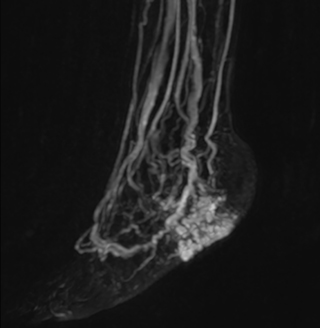

Another example is the foot examination for diabetic patients, which has improved dramatically. “The forefoot is generally difficult to image with MRI because of the inhomogeneities that the toes create – it’s hard to obtain good fat saturation in that area. Here, mDIXON made a huge difference right away, we obtain much better image quality,” Dr. Peña says. “Using mDIXON, Compressed SENSE and the dS FootAnkle coil, we have been able to reduce the scan time, so that we can now also include an additional 3D STIR sequence to visualize both arteries and veins in the foot.”

Avila adds: “In addition, since most of these patients are in a significant amount of pain, it’s important to perform the examination as quickly as possible. With Compressed SENSE and mDIXON we have been able to reduce the scan time from about 45 minutes to just 15 minutes. Not only does this improve patient comfort, we see that it also helps us acquire images without motion artifacts, which is critical to making a confident diagnosis.”

MRA of foot with 4D-TRAK XD

The images obtained with Ingenia Ambition show large coverage and high uniform signal. More vessels are visible than in a previous exam of the same patient on Achieva. The movies show a higher temporal resolution in the Ambition acquisition than in a previous Achieva 1.5T exam. Both exams use a FOV of 300 mm and voxel height and width of 0.78 mm.

Achieva 1.5T

2:30 min. TE 1 ms, TR 4 ms

Ingenia Ambition

4D Trak XD 1:54 min. TE 1ms, TR 3ms